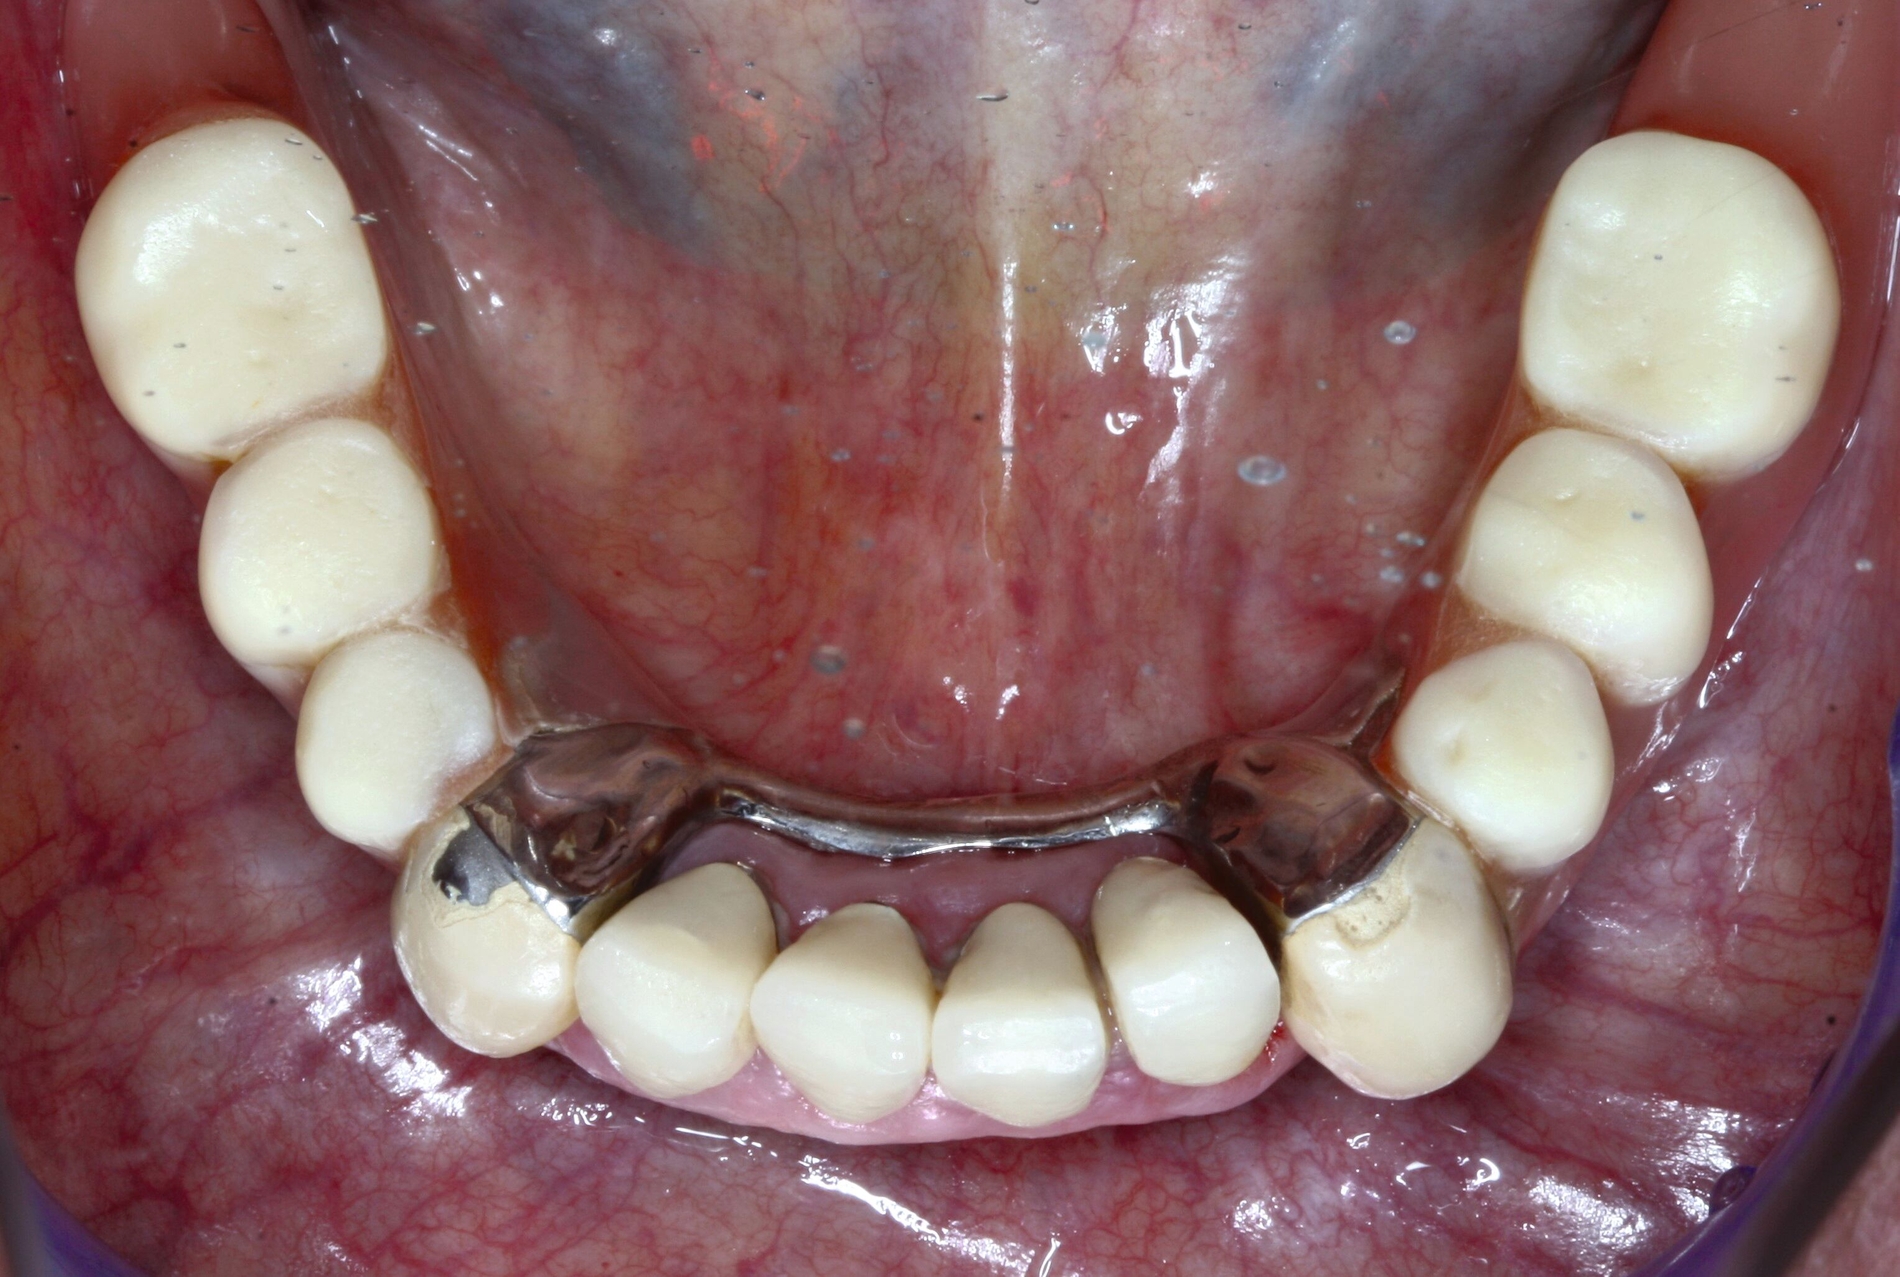

Sind größere Veränderungen am Zahnersatz erforderlich, so gilt es zu beachten, dass dieser zusammen mit der Zunge und der Wange einen fein abgestimmten Regelkreis fürs Kauen, Sprechen und Schlucken bildet. Bei Formveränderungen am Zahnersatz muss sich dieser Regelkreis neu programmieren – doch mit zunehmender Alterung nimmt diese Fähigkeit ab. Verbliebene wiedererkannte Konturen können helfen, die Adaptation an den umgestalteten Zahnersatz zu erleichtern. Es hat sich deshalb bewährt bei größeren Veränderungen des Mundraums, beispielsweise nach mehrfachem Zahnverlust, den bestehenden Zahnersatz eher umzuarbeiten, anstatt neu zu konstruieren. Im folgenden Beispiel wurden diese Überlegungen umgesetzt (Abbildung 8).

Der Verlust eines prothesendynamisch relevanten Pfeilerzahns konnte durch den größeren Abstand zur Doppelkrone mithilfe eines Locators ausgeglichen werden. Das Implantat wurde interforaminär an der Position 44 simultan zur Extraktion des Zahnes 43 gesetzt. Die Prothese musste anschließend nur unterfüttert und die Locatormatrize einpolymerisiert werden. Die Behandlung konnte so mit einer Mindestzahl an notwendigen Behandlungsterminen durchgeführt werden (Abbildung 8).